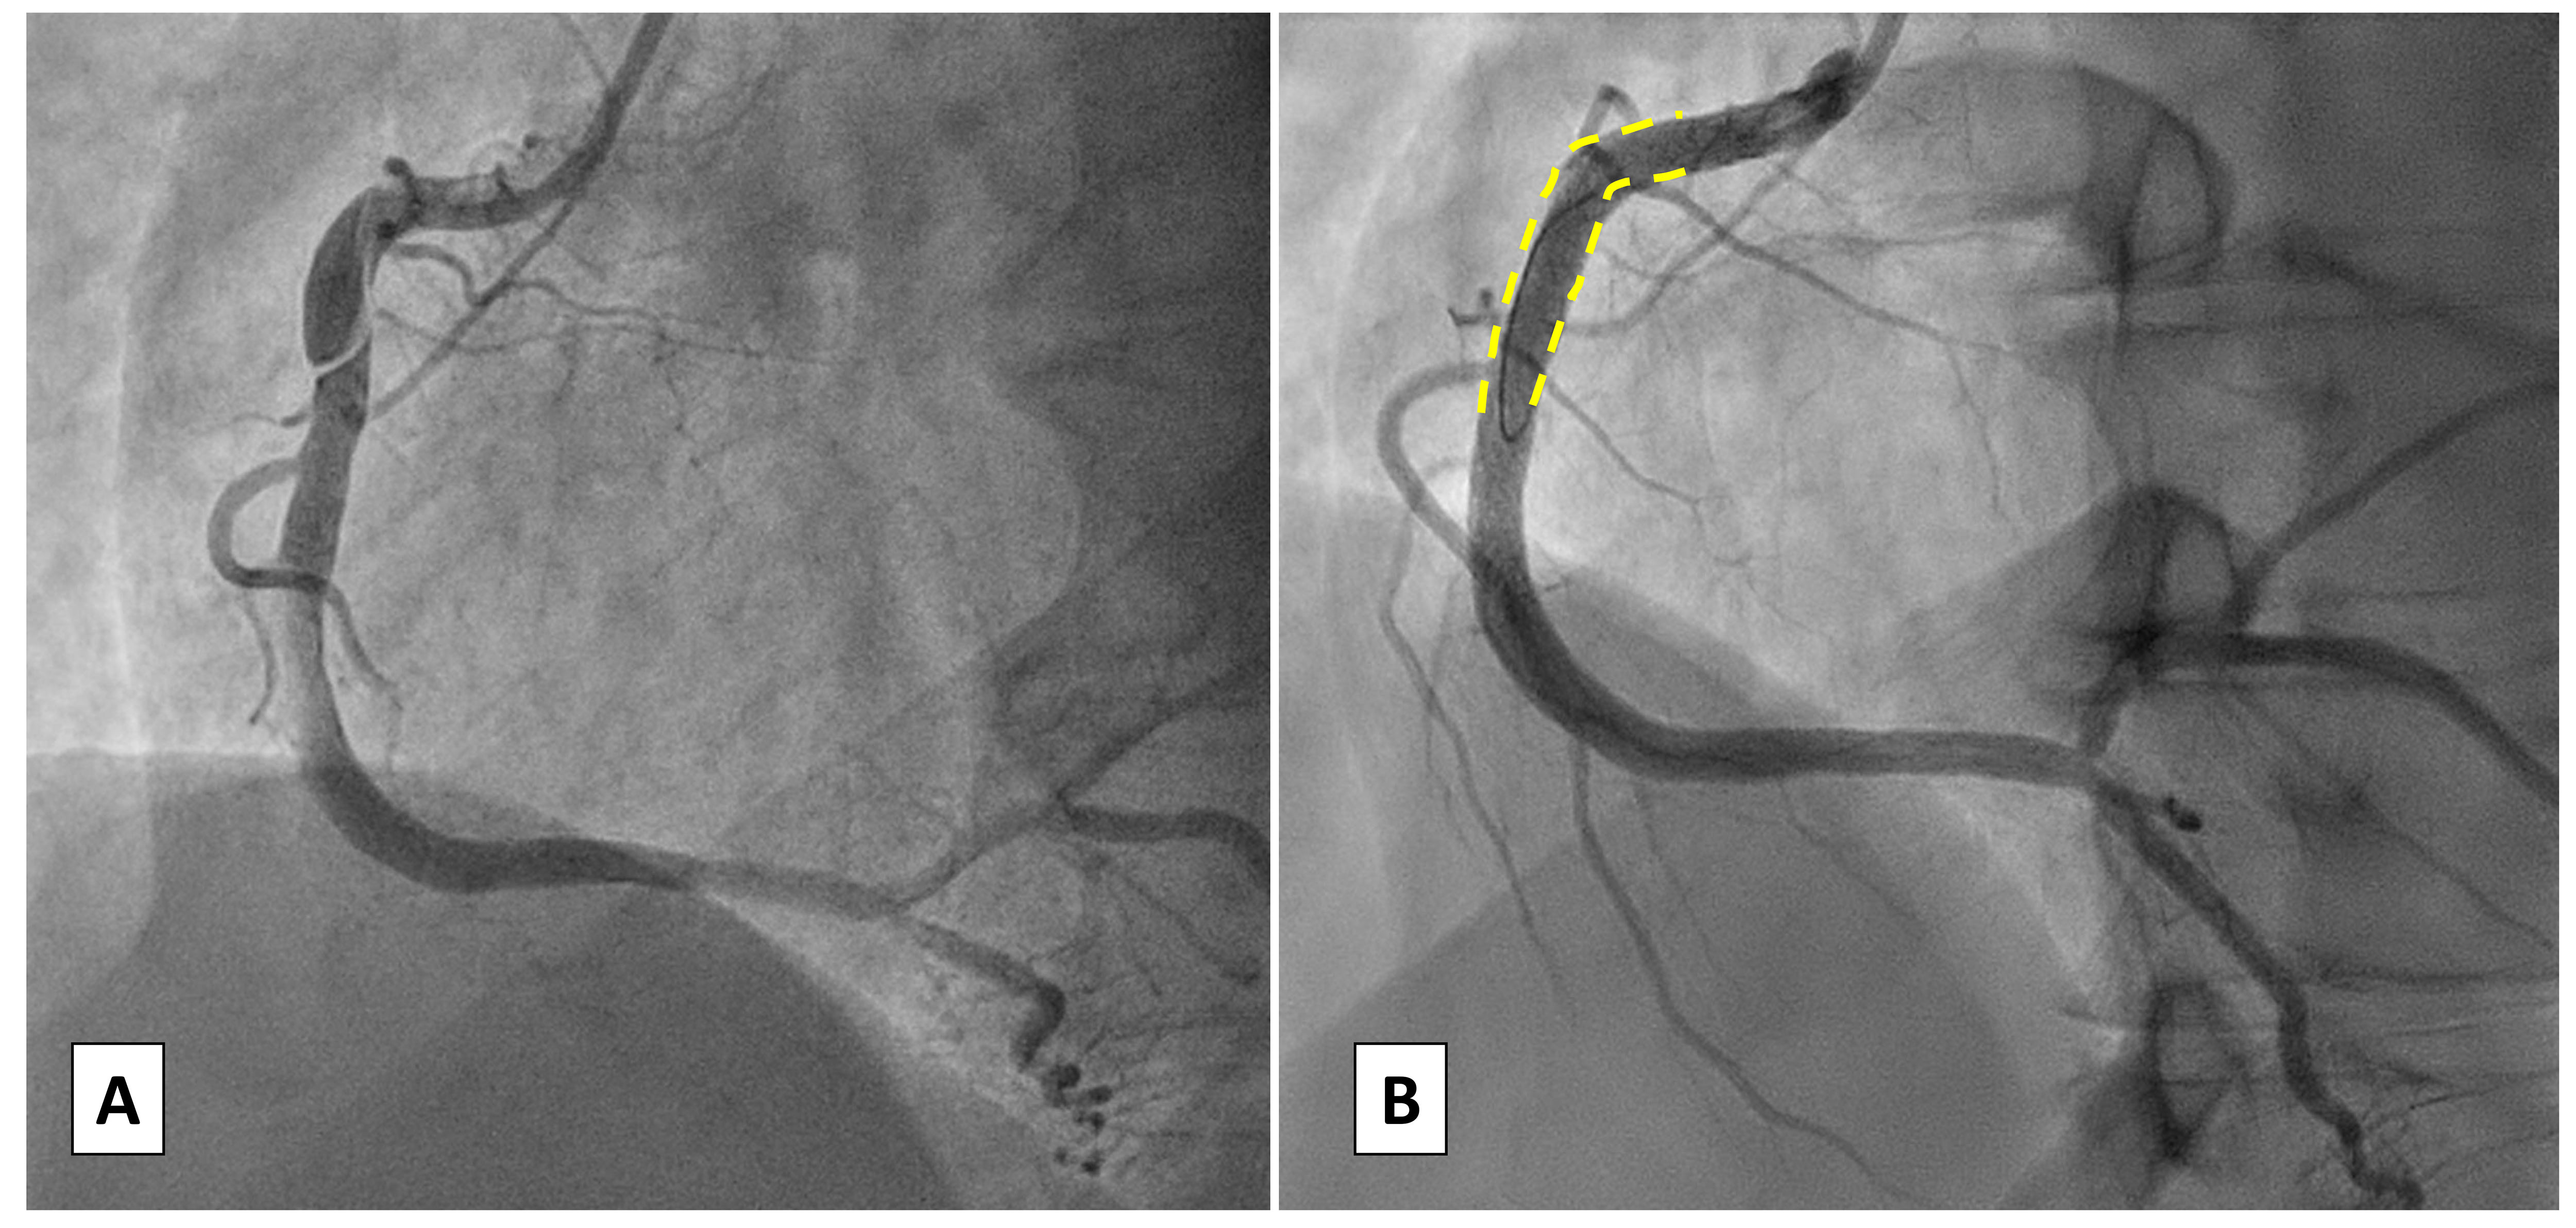

As most patients are young women without concomitant atherosclerotic disease, the use of stent sparing techniques may be preferable in order to avoid modifications of the coronary vessel physiology. As time goes by more and more evidence mainly from case reports or small observational cohorts appears in literature for SCAD in exactly the same way as for traditional angioplasty or peripheral interventions [50, 51]. In this sense the use of bioresorbable scaffolds (BRS) or a hybrid approach with bioresorbable scaffolds and drug eluting stents (BRS-DES) may be considered [52, 53, 54] to avoid long stenting (Fig. 3). In addition, balloon only strategies such as a cutting or drug coated balloon (DCB) may be performed. A cutting balloon may be considered for focal lesions, preferably in a proximal location to drain the intramural hematoma [55, 56]. In a recent review of 32 published cases [57] a cutting balloon resulted a favorable and safe strategy: TIMI 3 flow was restored in almost 85% of cases, despite requiring additional stenting in 37.5%. However, in literature case reports of cutting balloon strategies often report short follow-up length, thus only limited evidence is available on the effectiveness of this approach. Regarding drug coated balloons, scarce data are available and stem from experiences of these tools in iatrogenic dissection healing. The employment of DCB with longer balloon inflation may be considered in case of confirmed intimal tear dissection (“inside-out” mechanism) [58].

Fig. 3.

Case 2: Man, 51 yo, presenting with STEMI with evidence of SCAD of the left main involving also proximal left anterior descending artery (LAD) and circumflex artery (Cx), confirmed at intravascular ultrasound (IVUS) imaging. Given the young age and the need for an urgent interventional treatment a hybrid approach with bioresorbable vascular scaffolds (BVS) and single drug-eluting stent (DES) on left main (LM) was adopted.